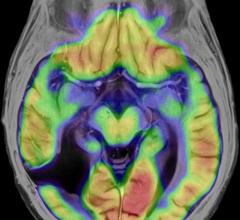

Neuro Imaging

Neuro imaging produces images of the structure or activity of the nervous system, usually the brain. It uses techniques like magnetic resonance imaging (MRI) and computerized tomography (CT).